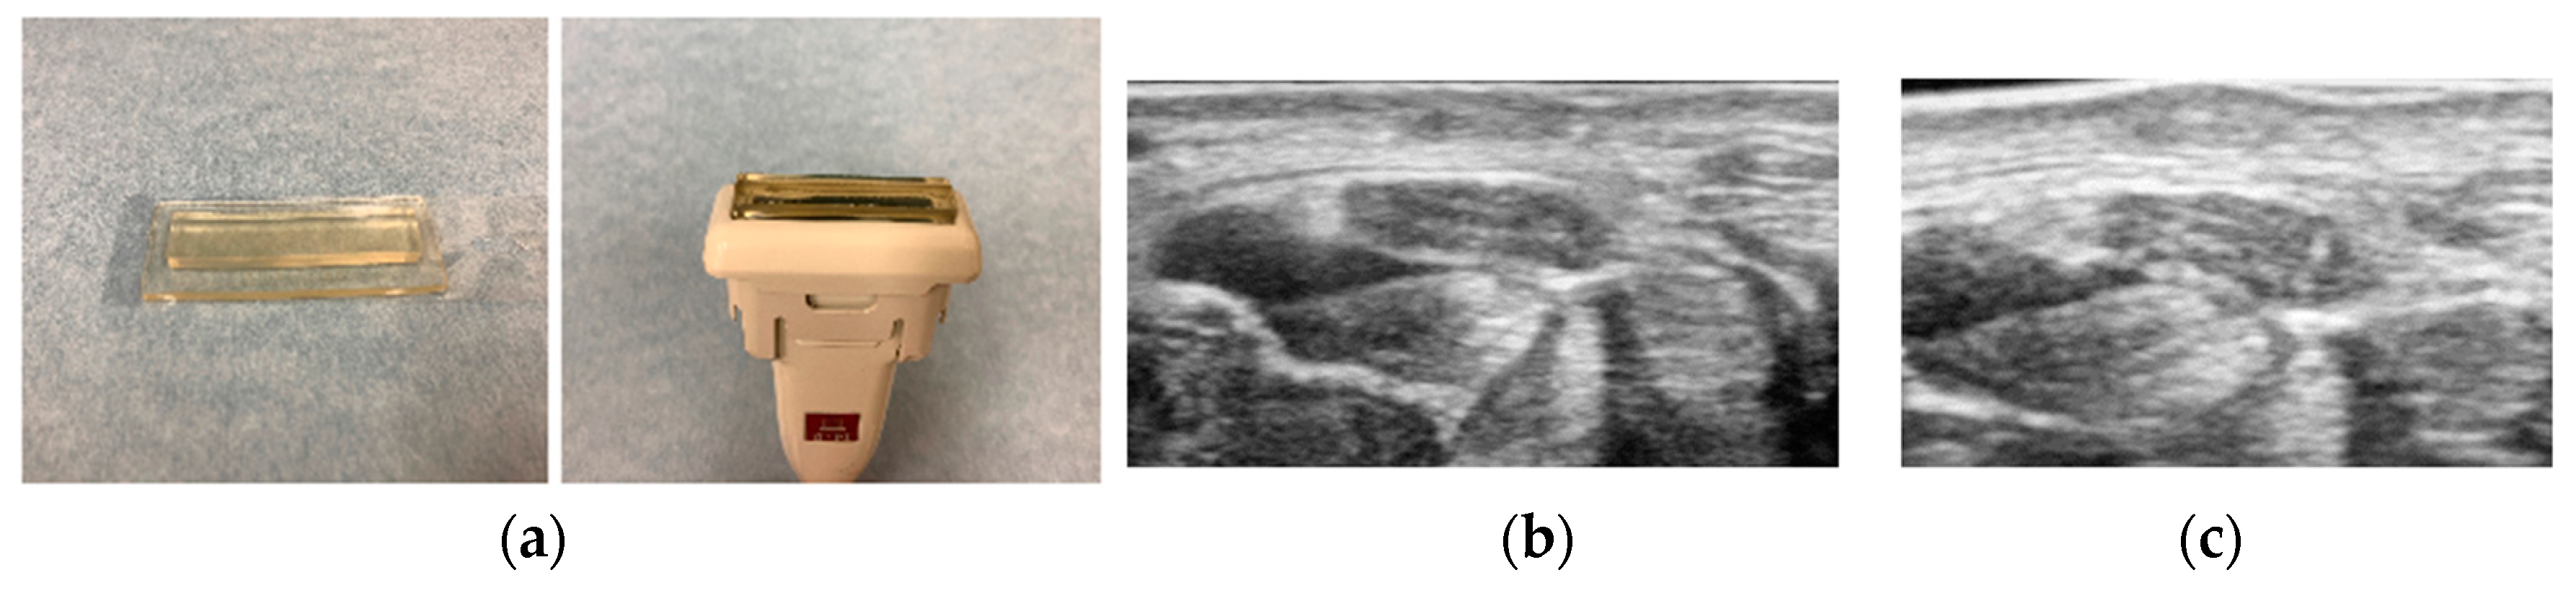

- Yoshii, Y.; Villarraga, H.R.; Henderson, J.; Zhao, C.; An, K.N.; Amadio, P.C. Ultrasound assessment of the displacement and deformation of the median nerve in the human carpal tunnel with active finger motion. J. Bone Joint Surg. Am. 2009, 91, 2922–2930. [Google Scholar] [CrossRef]

- Van Doesburg, M.H.; Henderson, J.; Yoshii, Y.; Mink van der Molen, A.B.; Cha, S.S.; An, K.N.; Amadio, P.C. Median nerve deformation in differential finger motions: Ultrasonographic comparison of carpal tunnel syndrome patients and healthy controls. J. Orthop. Res. 2012, 30, 643–648. [Google Scholar] [CrossRef]

- Yoshii, Y.; Ishii, T.; Tung, W.L.; Sakai, S.; Amadio, P.C. Median nerve deformation and displacement in the carpal tunnel during finger motion. J. Orthop. Res. 2013, 31, 1876–1880. [Google Scholar] [CrossRef]

- Yoshii, Y. Dynamic analysis of ultrasound image for the diagnosis of carpal tunnel syndrome. Kansetsugeka 2015, 34, 636–643. [Google Scholar]